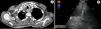

The patient was a 71-year-old man, smoker, with an alcohol intake of 30g/day, who presented with a 2-month history of dysphagia associated with constitutional syndrome. Physical examination was normal. Laboratory tests were unremarkable, apart from a total bilirubin of 1.3mg/dl. Computed tomography (CT) detected a 33mm×26mm×48mm mass in the upper third of the esophagus (Fig. 1A). Gastroscopy showed stenosis of the cervical esophagus, apparently extrinsic, that prevented advancement of the endoscope. During the transesophageal endoscopic ultrasound (EUS), stenosis of the esophageal lumen made it difficult to introduce the endoscope, and sampling by fine needle aspiration was not optimal. Aspiration performed in the area most proximal to the lesion showed only atypical cells.

Since a diagnosis could not be made through the digestive tract, the possibility of a diagnostic approach using transtracheal ultrasound-guided fine needle aspiration (EBUS-FNA) was studied. Following endoscopic examination, we detected a protrusion of the pars membranacea in the upper third of the trachea. Using ultrasound, a 25mm×32mm retrotracheal mass was identified 2cm from the vocal cords (Fig. 1B), which was aspirated twice. After histopathological study of the samples, including immunohistochemistry studies (positive for cytokeratin 5 and p63 and negative for cytokeratin 7 and TTF1), esophageal squamous cell carcinoma was diagnosed.